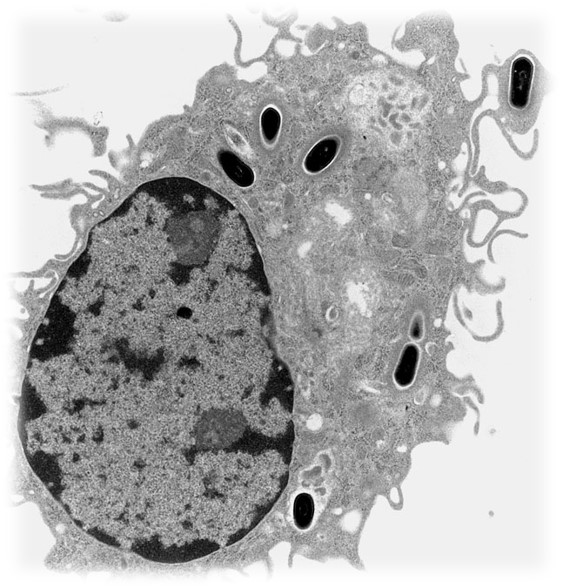

درم

- اصلی ترین توده پوستی

- بافت همبند فیبروالاستیک

–سلولهای اصلی:

- فیبروبلاست

- ماکروفاژ

- ماستسل